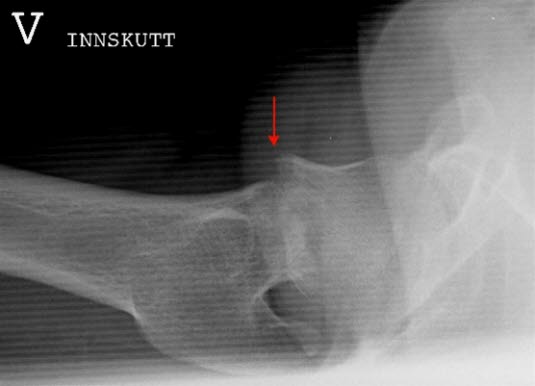

Collum femoris fraktur, innskutt

Innskutt sidebilde av venstre hofte med medial collumfraktur (pil)